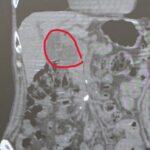

総合病院に通院している90代の方

普段高血圧で総合病院に通院している90代の元気な方です。 あしのむくみが気になり、ご家族と受診されました。 CTで膵臓に腫瘍を認めます 普段、総合病院、大学病院に通院しているのに 気になることをお話されない方がとても多いと感じています。 それは、患者さんが悪いわけでなく 医師が、患者さんが気になることを聞き出さないからです。 医師と患者さんの関係が いつもの薬 だけでつながっているだけでは 気軽...